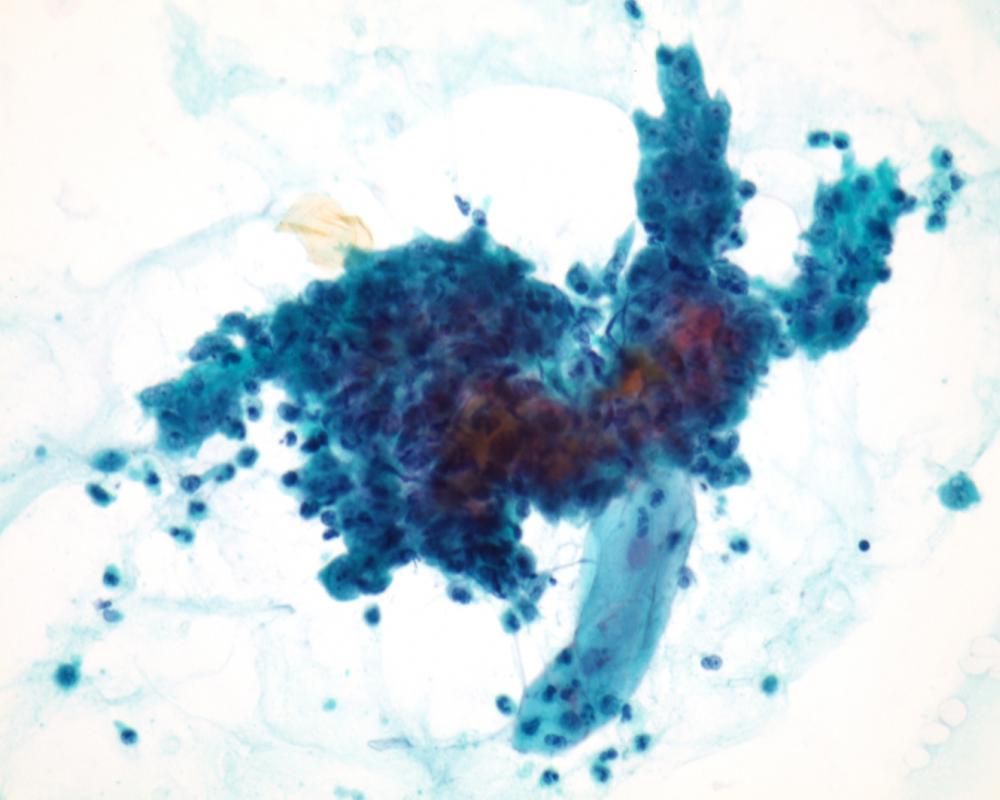

第36回日本臨床細胞学会九州連合会学会(大分)スライドカンファレンス症例1

種別:婦人科

出題:熊本大学病院 病理部・病理診断科 塩田 拓也

| 年齢 | 40代 | 性別 | 女性 |

| 採取部位 | 子宮頸部 | 採取方法 | 擦過 |

| 検体処理法 | 従来法 |

臨床所見

既往歴:薬剤アレルギー(Stevens Johnson症候群疑い)、尾てい骨骨折、高血圧症

現病歴:筋腫分娩が疑われ、診断・治療目的で当院紹介受診となった。

| 正解 | 5.腺扁平上皮癌 |

▼選択肢及び投票結果

| 1.高度扁平上皮内病変(HSIL) | 0件 | (0.0%) | |

| 2.上皮内腺癌(AIS) | 5件 | (7.8%) | |

| 3.重層性粘液産生上皮内病変(SMILE) | 50件 | (78.1%) | |

| 4.腺癌 | 5件 | (7.8%) | |

| 5.腺扁平上皮癌 | 4件 | (6.2%) | |

| 投票総数 | 64件 | (100%) |